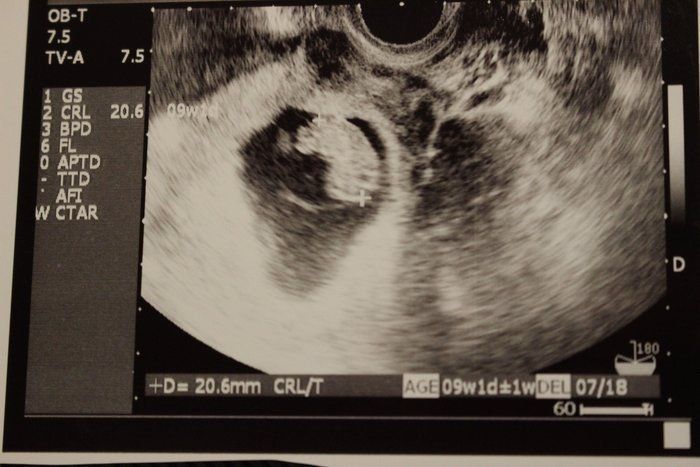

Amiさんの妊娠9週目のエコー写真

この写真から、胎嚢の中の我が子が二頭身になっていることがわかります。赤ちゃんの大きさは18.9mm。ちょうど枝豆一粒くらいの大きさですが、この時期は胎芽から胎児へ移行する時期のようです。それほど体調に変化もなく、「本当に自分のおなかに赤ちゃんがいるのか」と不思議な気持ちでした。